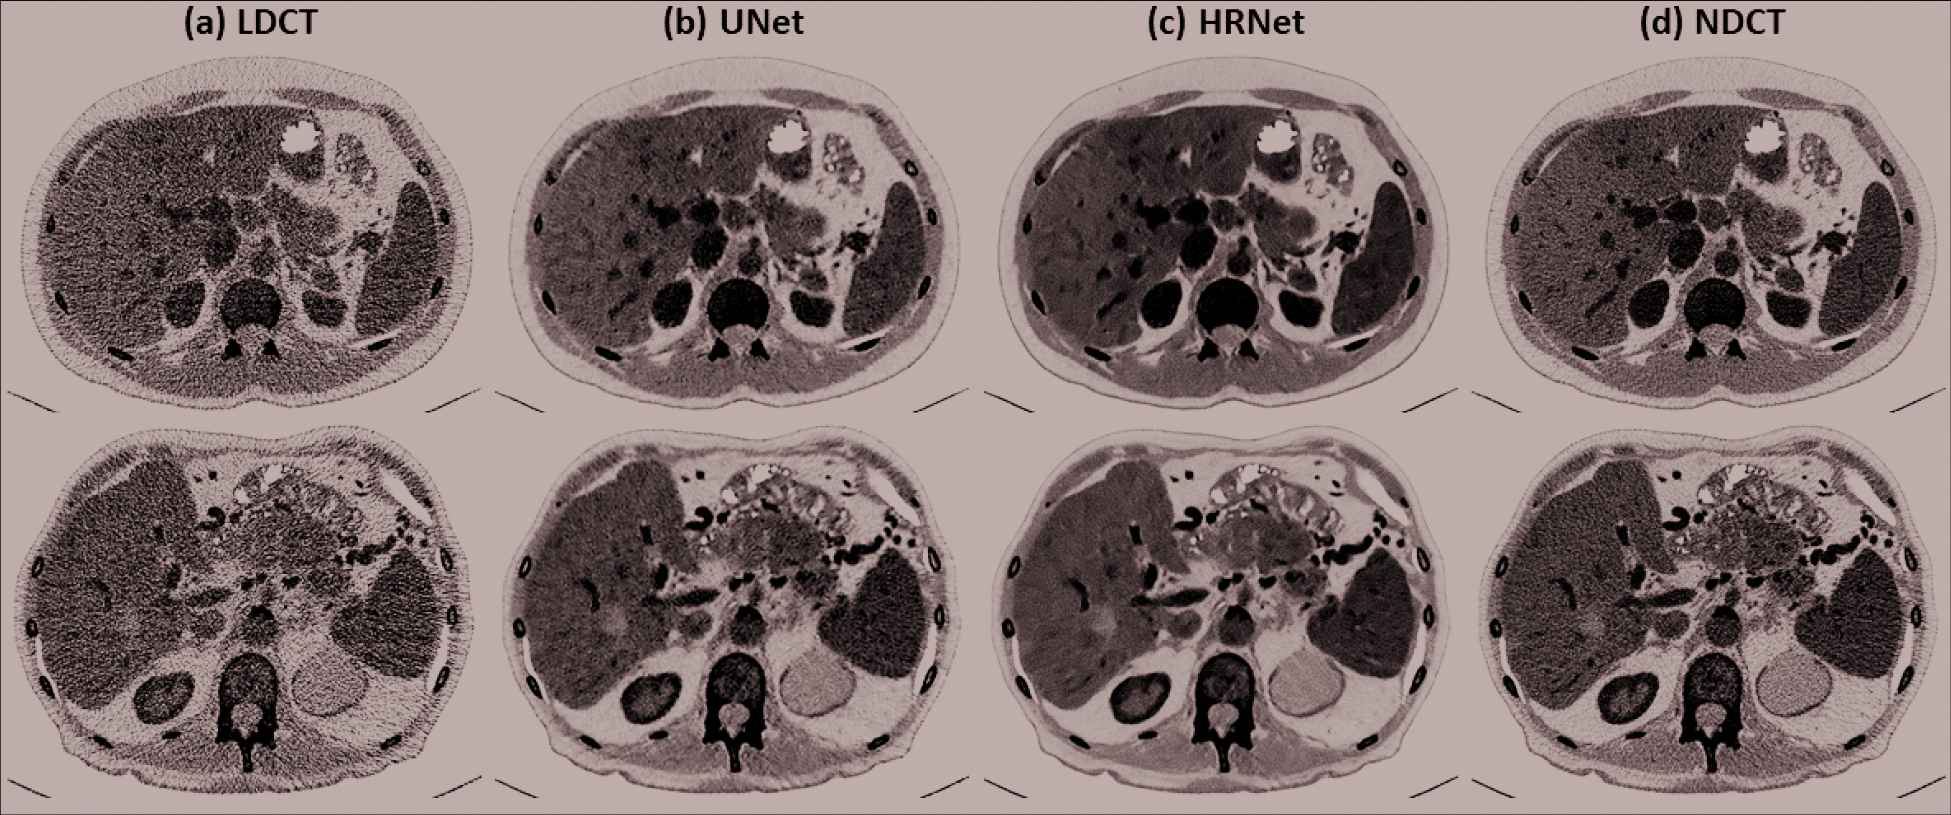

Figure 3 demonstrates the denoised results for the liver organ. The strong noise in the LDCT image overwhelms the fine vessels in the liver. Both denoisers suppressed the noise effectively. Observing the zoomed-in view in the second row of Figure 3 reveals that the HRNet-based denoiser produced an image with more details, thus suggesting higher resolution, than the U-Net–based denoiser. Moreover, the noise in the image associated with the HRNet-based denoiser is weaker than in the image from the U-Net–based denoiser, which indicates the HRNet's stronger denoising ability. The red arrows indicate that some of the vessels in the image from the HRNet-based denoiser can be more easily distinguished than even those in the NDCT image, which also suffers from the quantum noise.

Denoised results for the slice corresponding to the liver organ. (a) LDCT, (b) U-Net, (c) HRNet, and (d) NDCT. Images in the second row are the zoomed-in views for the contents in the first row, corresponding to the region of interest indicated by the solid green box. Display window: [−160, 240] HU.